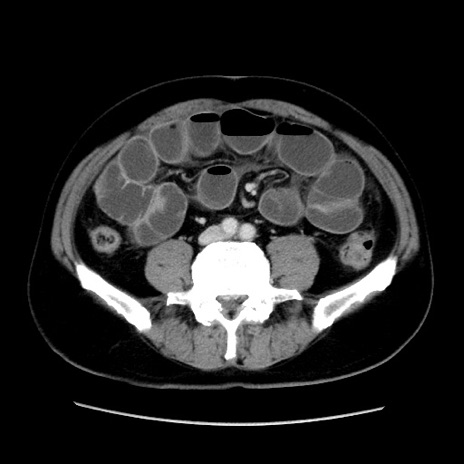

症例16(横断像)

冠状断像

【症例】 70歳代男性

【主訴】 腹痛、嘔吐

【現病歴】 約1ヶ月前より間欠的に腹痛と嘔吐あり、当院消化器内科を受診したところCTで多発する肝臓のLDAを指摘され、精査中であった。以降は消化器症状は安定していたが、2日前より嘔気と腹痛があり、同日より排便・排ガスが消失した。改善認めず、 本日、救急外来を受診した。

【身体所見】意識清明・会話良好、BT 36.3℃、BP 127/80mmHg、 P 80bpm、腹部:膨満あり、平坦・軟、上腹部正中および下腹部正中に圧痛あり、反跳痛なし、筋性防御なし。

【データ】WBC 7200、CRP 0.77